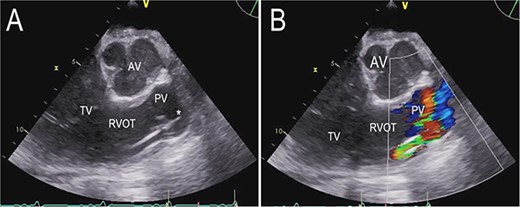

On the second postoperative day the patient showed hemodynamic impairment with signs of right ventricular failure. A temporary percutaneous RVAD was implanted with two cannulas via the right internal jugular vein (IJV) and the right femoral vein (FV). Despite RV support, LVAD flow did not increase and hemodynamic instability failed to improve. Transthoracic echocardiography revealed severe pulmonary insufficiency caused by the cannula of the RVAD. The blood recirculated in the congested right ventricle (Fig. 2, Videos S2 and S3 in the Supplementary Material online).

Transthoracic echocardiogram after implantation of a percutaneous RVAD with two cannulas via the right IJV and right FV. Parasternal long-axis view demonstrating the cannula position in the pulmonary valve (A). Color Doppler transthoracic echocardiogram after implantation of a percutaneous RVAD with two cannulas via the right IJV and right FV. Parasternal long-axis view demonstrating severe pulmonary regurgitation due to cannula position in the pulmonary valve (B). AV (aortic valve), PV (pulmonary valve), RVOT (right ventricular outflow tract), TV (tricuspid valve), * tip of cannula.